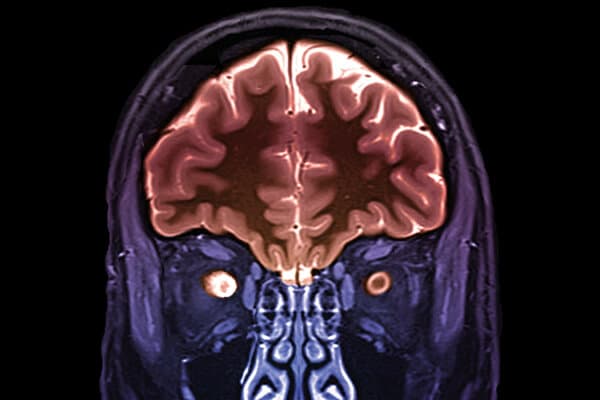

Des troubles de la vision pouvant aller jusqu’à la cécité peuvent être les signes d’une névrite optique. Les diagnostics différentiels sont nombreux. En Europe la cause la plus fréquente est une maladie inflammatoire auto-immune, en particulier la sclérose en plaques. En Allemagne, elle touche quelque 300 000 personnes, principalement des femmes.

Critères diagnostiques et évolution de la sclérose en plaques